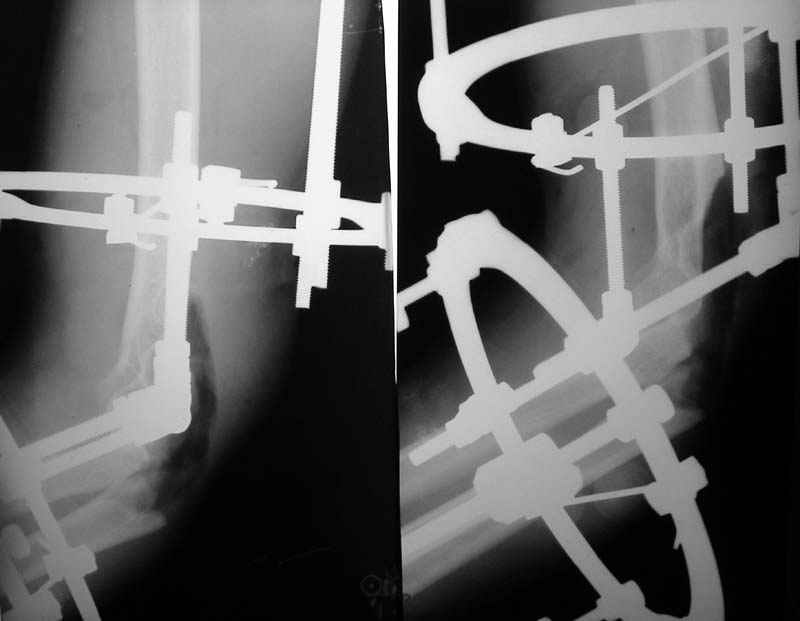

Операция - ПХО, ЧКО АВФ (см.приложение).

Репонировать фрагменты локтевой и плечевой кости не представилось возможным (по сути <каша> из мелких осколков сомнительной жизнеспособности), резекция головки лучевой кости, иссекли мягкие ткани, кожа зашита почти без натяжения, дренажи, АВФ.